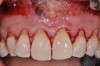

A 24-year-old, nonsmoking man presented for correction of gingival clefting and recession in the maxillary left anterior sextant (Figure 6). The patient’s medical history was noncontributory. After consultation and presenting various options to the patient to correct the localized recession, the patient opted for the use of acellular dermal matrix tissue rather than harvesting tissue from his palatal area.

After administration of an appropriate local anesthetic, a laser-assisted split-thickness vestibuloplasty was performed superior to the mucogingival junction from the right central incisor to the left first premolar region (Figure 7). Prior to any incisions being performed, a 20-mm x 40-mm dermal matrix graft (Puros Dermis), a 0.8-mm to 1.7-mm thick piece of tissue, was trimmed to appropriate length and width to correct the gingival defect present (Figure 8). The tissue graft was sized to 6 mm in height and spanned to the mesial line angle of the left central incisor to the distal line angle of the left canine area. The dermal matrix graft was rehydrated with the patient’s own platelet-rich plasma solution, which was harvested from 20 cc of whole blood collected immediately prior to the surgical procedure (Figure 9).

Fig 6. Pretreatment clinical view, maxillary left anterior sextant, of case presented.

Figure 6

Fig 7. Laser-assisted split-thickness vestibuloplasty performed.

Figure 7